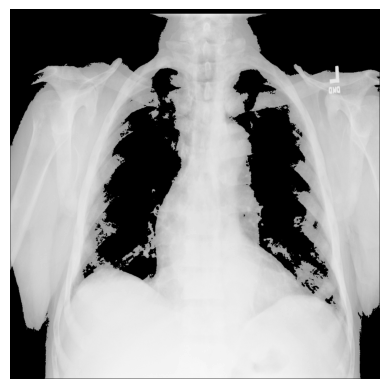

3.您可以使用 NumPy 创建不同的条件蒙版np.where()- 例如,我们只使用像素超过特定阈值的图像值:

# The threshold is "greater than 150"

# Return the original image if true, `0` otherwise

xray_image_mask_noisy = np.where(xray_image > 150, xray_image, 0)

plt.imshow(xray_image_mask_noisy, cmap="gray")

plt.axis("off")

plt.show()

# Return `1` if true, `0` otherwise

xray_image_mask_less_noisy = np.where(xray_image > 150, 1, 0)

plt.imshow(xray_image_mask_less_noisy, cmap="gray")